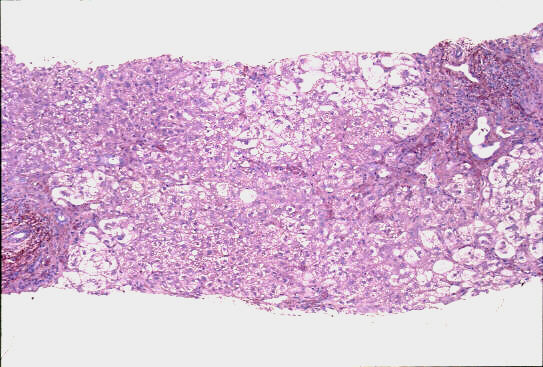

- 門脈域;中等度までの線維性拡大、中等度までの単核球主体の炎症性細胞浸潤、小葉間胆管の障害像、細胆管増生、胆汁栓

- 実質域;架橋形成性壊死 (bridging hepatic necrosis)、肝細胞の風船様膨化と再生性肝細胞、小ないし中滴性脂肪沈着を部分的にみる、羽毛状変性と風船様膨化、合胞性多核巨細胞の出現、ロゼット形成(偽腺管構造)、胞体内凝集傾向、核内空胞

肝細胞にビリルビン色素、Ground-glass所見は認めない

HBsAgオルセイン;陰性(Marcophage or Kupffer's cellsに陽性;Ce-L)

病理組織診断;急性肝炎、架橋形成性壊死を伴う(重症型)

Acute hepatitis with bridging necrosis